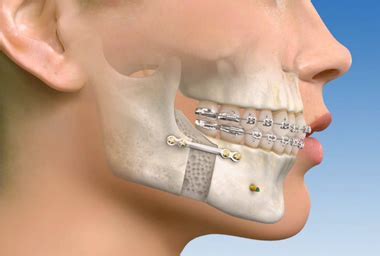

Disadvantages Of Jaw Wiring Maxillofacial Hardware Surgery T